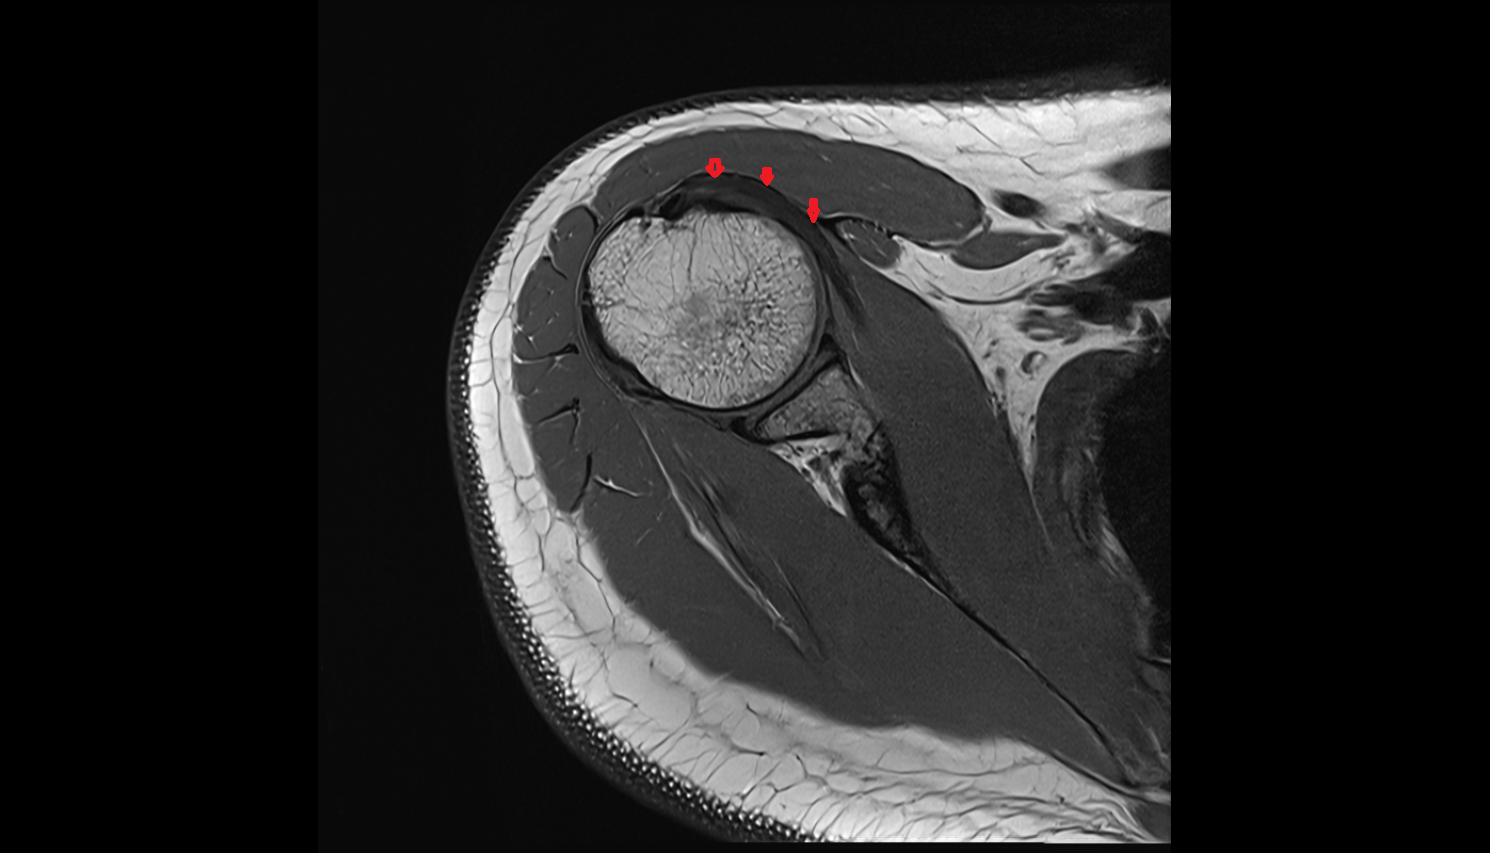

- Supraspinatus tendon